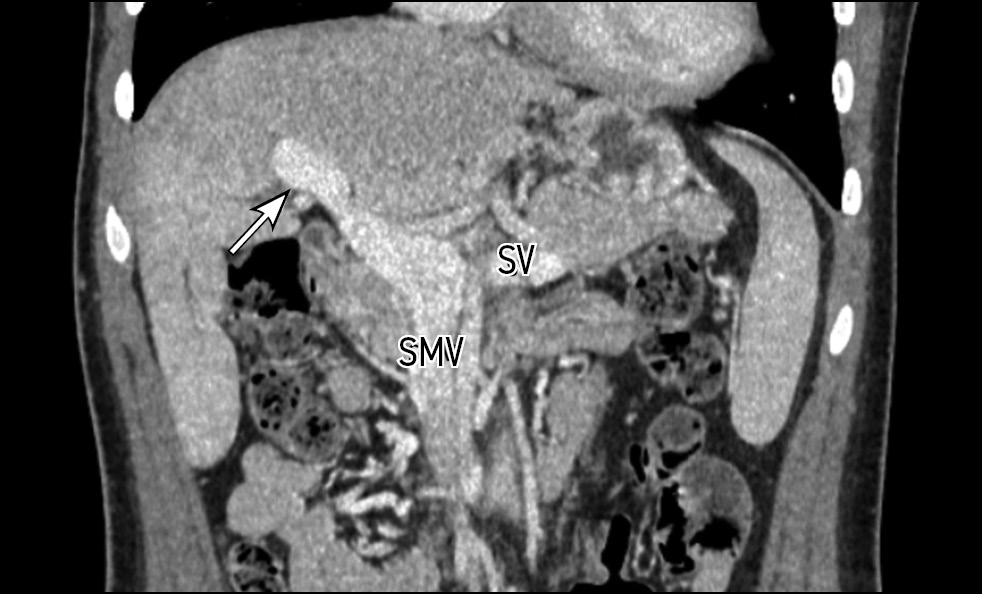

Contrast-enhanced abdominal computed tomography (CT) with multiplanar reconstruction revealed that the splenic (12 mm in diameter (Figure 1)) and superior mesenteric veins fused together, forming a portal vein conduit dilated to 28 mm in diameter (Figures 2 and 3), flowing directly into the inferior vena cava (IVC), bypassing the porta hepatis (Figure 4). Moreover, moderate liver and spleen enlargement and weak heterogeneous contrast enhancement of the liver parenchyma were noted. The findings were consistent with Abernethy malformation type Ib.

Fig. 2. Contrast-enhanced CT, portal phase, coronal view. Splenic (SV) and superior mesenteric (SMV) veins fused together, forming a portal vein conduit (white arrow).